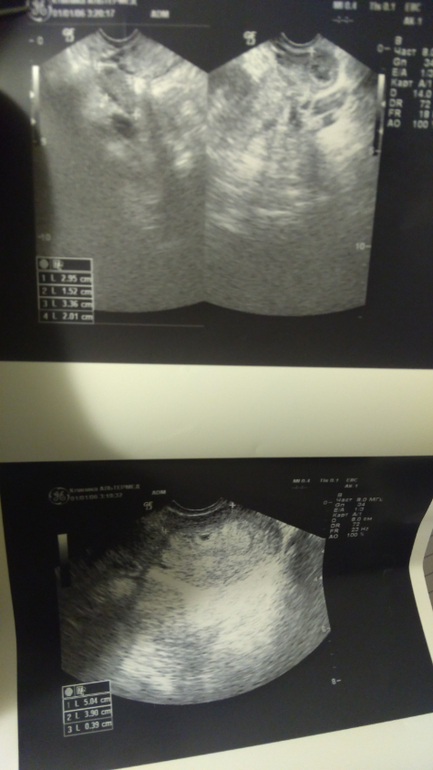

Вопросы про УЗИ, обследования и анализы: что, где, как, когда?Девочки, привет. Сходила на УЗИ сегодня, поставили угрозу, т.к. низко расположено плодное яйцо. И есть гематомы из-за отслойки хориона. Одно плодное яйцо 4 мм.

А что там еще отслаиваться может? может я что-то перепутала, но она сказала, что из-за этого гематомы небольшие

Отслаиваться может само плодное яйцо, из-за этого могут быть гематомы. Вы себя вообще как чувствуете?